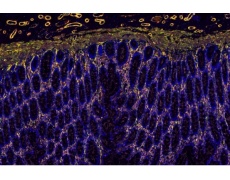

切片全景掃描(熒光單標(biāo)雙色)